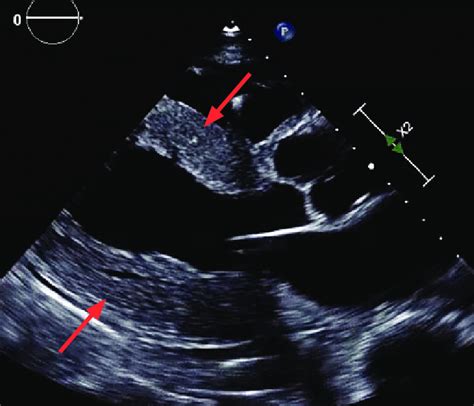

Alright, let’s get down to the nitty-gritty of long axis view echo probe position . The standard approach starts with placing the probe in the third or fourth intercostal space, just to the left of the sternum. Now, here’s the kicker: the orientation marker on your probe (usually a notch or a light) should be pointing towards the patient’s right shoulder. This is crucial because it aligns the ultrasound beam in the correct plane to capture the long axis view of the heart. Once you’ve placed the probe, start by fanning and tilting it slightly. Fanning involves making small, sweeping motions from side to side, while tilting means angling the probe up or down. These subtle adjustments can make a huge difference in image quality. You’re essentially hunting for the best acoustic window – the spot where the ultrasound waves can penetrate the chest wall with minimal obstruction. When you find that sweet spot, you should see the left ventricle appearing as an elongated chamber with the mitral valve opening and closing. The aortic valve will be visible at the top of the left ventricle, and the left atrium will be behind the mitral valve. Don’t worry if it doesn’t look perfect right away. It takes practice and a bit of finesse to get it just right. Keep adjusting the probe position and angle until you get a clear and comprehensive view of all the key structures. Remember, patience is key, and every patient’s anatomy is a little different, so be prepared to adapt your technique as needed.

To really nail the long axis view echo probe position , let’s look at some real-world examples. Imagine you’re examining a patient with suspected aortic stenosis. By obtaining a clear PLAX view, you can visualize the aortic valve and assess the degree of narrowing. You can also use Doppler imaging to measure the velocity of blood flow across the valve, which helps quantify the severity of the stenosis. Or, consider a patient with heart failure. The PLAX view allows you to assess the size and function of the left ventricle. You can measure the ejection fraction, which is a key indicator of systolic function, and evaluate for signs of diastolic dysfunction. In patients with mitral valve prolapse, the PLAX view can show the characteristic bowing of the mitral valve leaflets into the left atrium during systole. These are just a few examples of how the long axis view can be used to diagnose and manage a wide range of cardiac conditions. By studying case studies and real-world examples, you can develop a deeper understanding of how to apply your knowledge and skills in clinical practice. So, keep practicing, keep learning, and keep exploring the fascinating world of echocardiography.